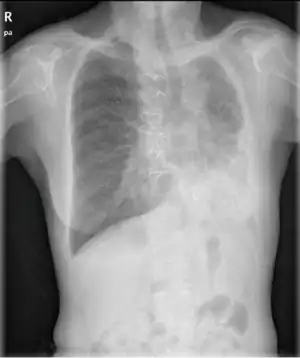

| Chest radiograph of a woman with unilateral pulmonary agenesis | |

- Chest X-ray is effective in detecting the traits of lung herniation.[1] The unaffected side of lung tends to undergo hypertrophy, and move towards the empty space in the chest wall on the opposite side.[1] This herniation could be indicated by fluoroscopy.[1] With age increasing, the herniation progresses and ease its detection.[1]